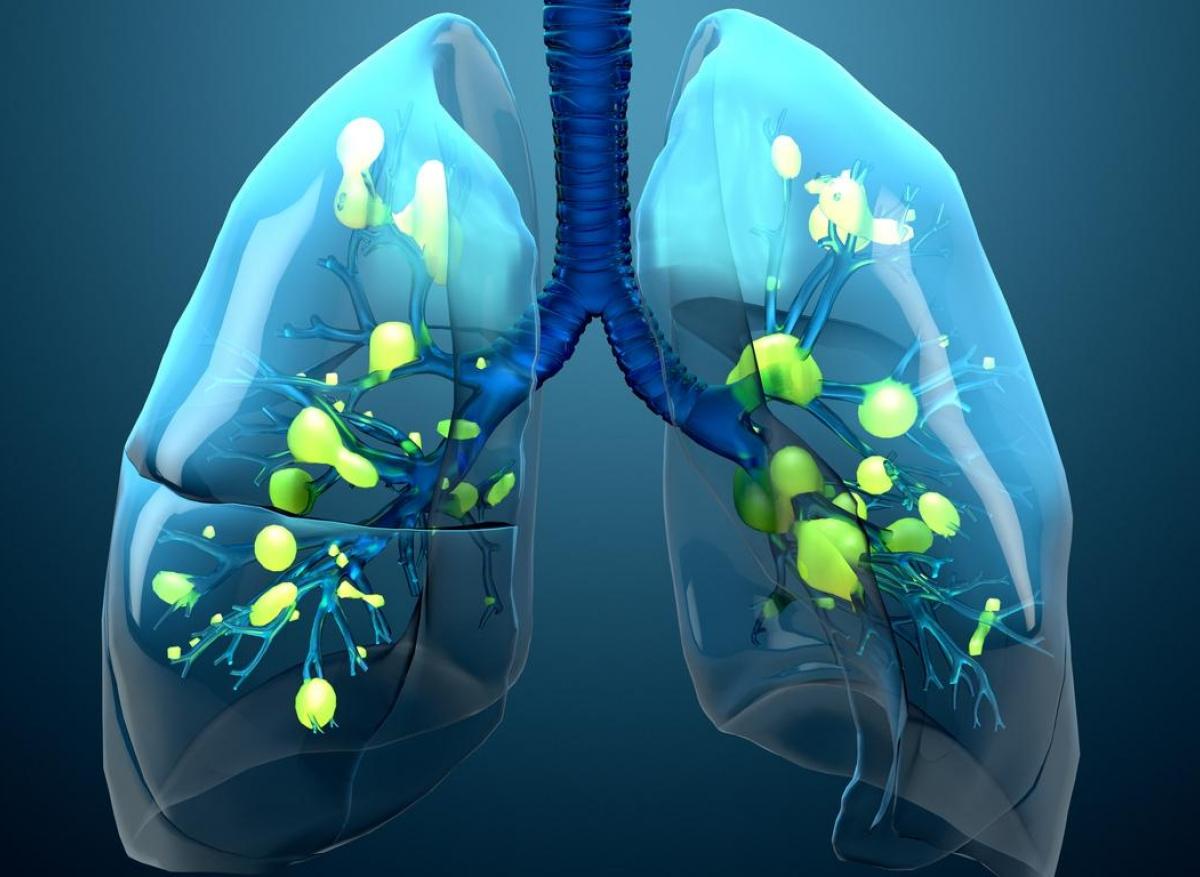

Prise en charge des infections des voies respiratoires basses de l'immunocompétent. Partie concernant les définitions, l'épidémiologie et les éléments du diagnostic Managing lower.

Infections respiratoires basses de l'enfant. Le diagnostic d'infection respiratoire chez l'enfant repose sur une triade symptomatique : fièvre, toux et difficultés respiratoires d'intensité.